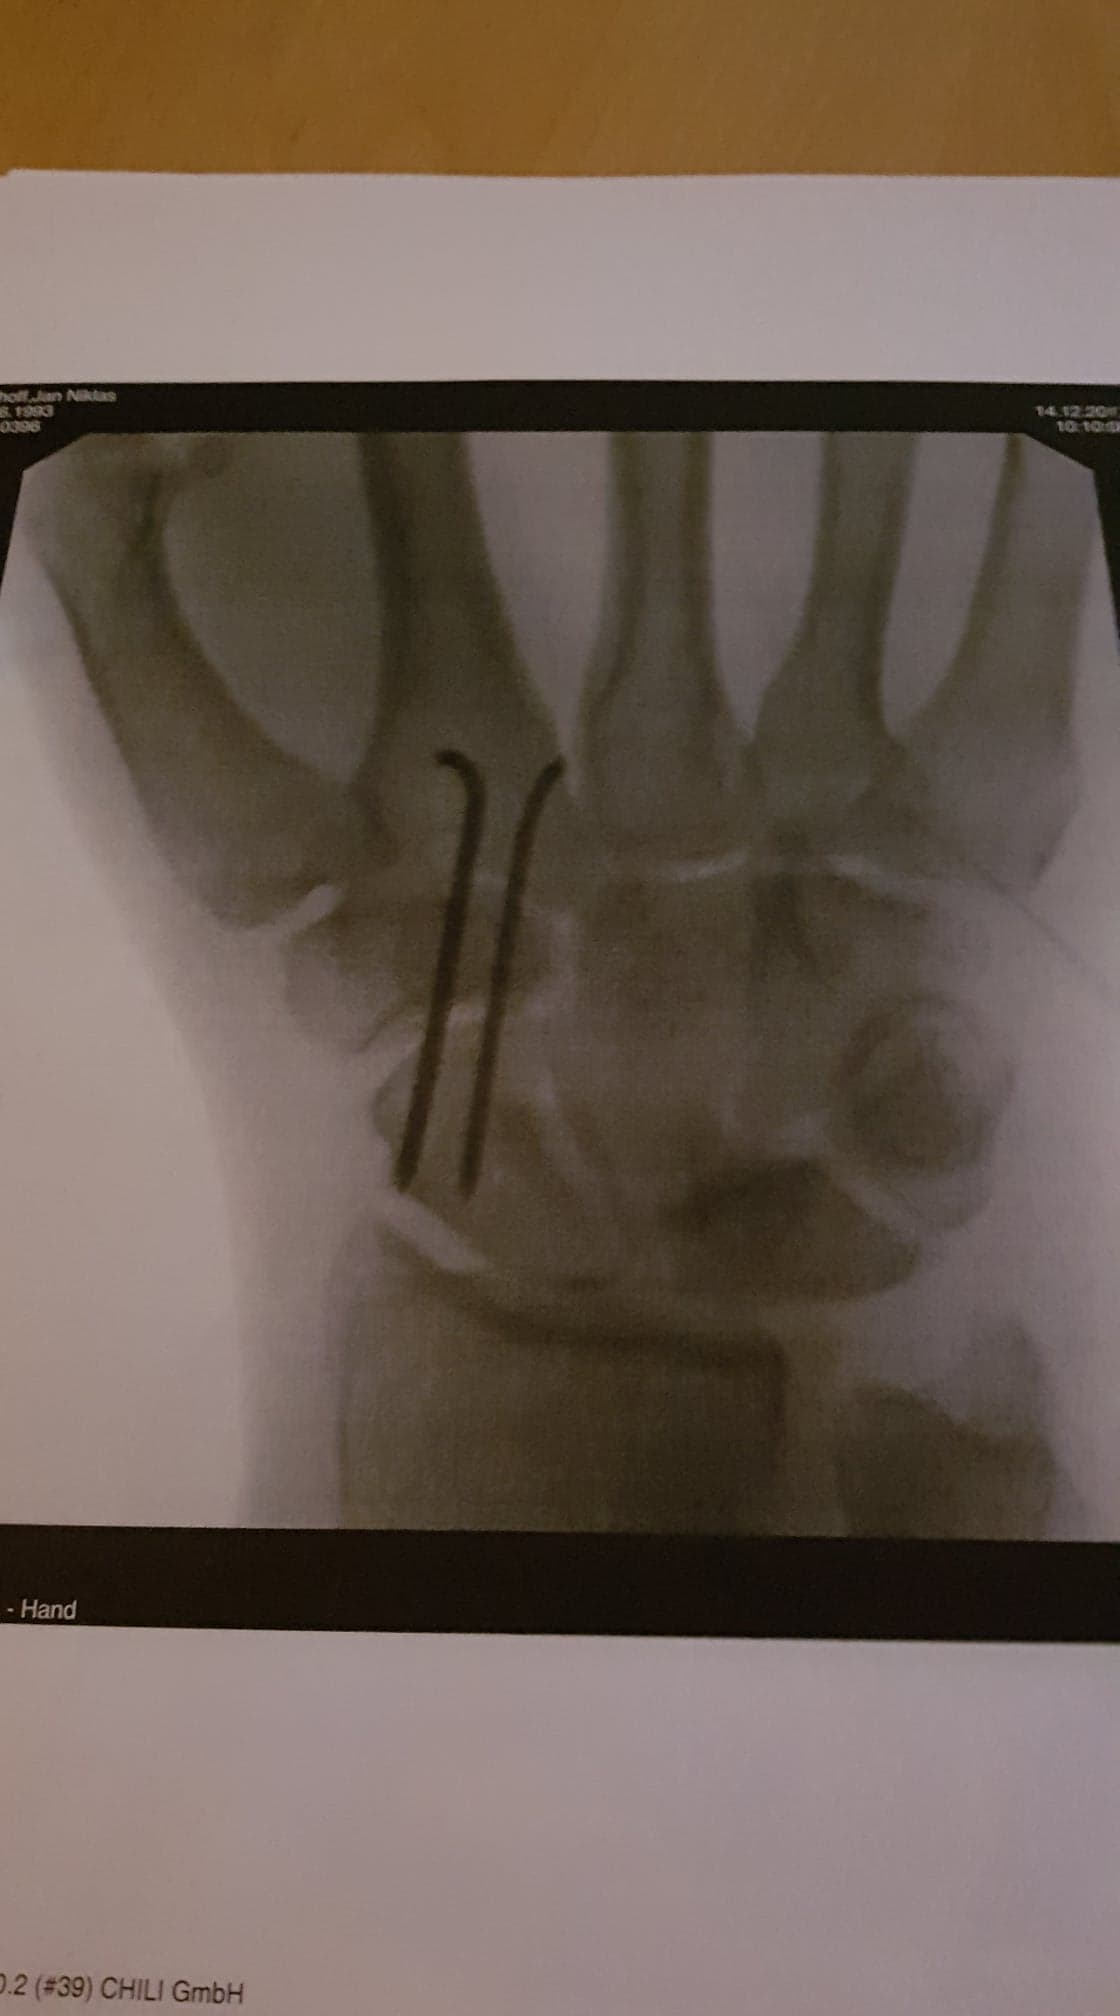

Temporäre ST Transfixation.

Dies war ein kleiner Eingriff, der in der Tagesklinik gemacht wurde. 13.12.2017.

Auch dies ist gut verlaufen.

Nachdem ich 2 Wochen den Gips getragen hatte, habe ich der Hand die Bewegung gegeben, die sie braucht. Keine Physio. Ein Kontrolltermin sollte nach 3 Monaten statt finden.Also ging es im März nach meinem 1 Jährigem Jubiläum wieder in den Süden. MRT mit Kontrastmittel und CT.